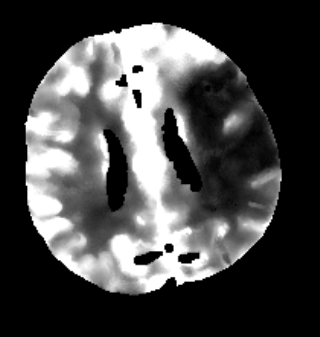

Des Weiteren ist mRay in der Lage eine Verarbeitung von Bildern durchzuführen und so Veränderungen bzw. Anomalien in Geweben zu finden, zu visualisieren und zu quantifizieren. Das Bildverarbeitungsmodul mRay VEOcore kann verwendet werden, um Bilder des Gehirns von Bildgebungsmodalitäten wie CT, Perfusions-CT oder MRT mit diffusionsgewichteter Auswertung (DWI) zu prozessieren. Als Ergebnis werden Kontrastveränderungen über die Zeit als farbige Perfusionskarten angezeigt, dies beinhaltet auch flussbasierte Parameter und Gewebeblutvolumen Berechnungen.

Die Perfusionsanalyse von Aufnahmen des Gehirns ermöglicht die Darstellung und Quantifizierung von minderdurchblutetem Gewebe (Penumbra), nicht-durchblutetem Gewebe (Kerngewebe) und dem Mismatch-Ratio zwischen den beiden Werten. Die berechneten Werte können der Unterstützung bei einer Entscheidungsfindung dienen, die auf der Beurteilung des Ausmaßes der Schädigung von Geweben basiert.